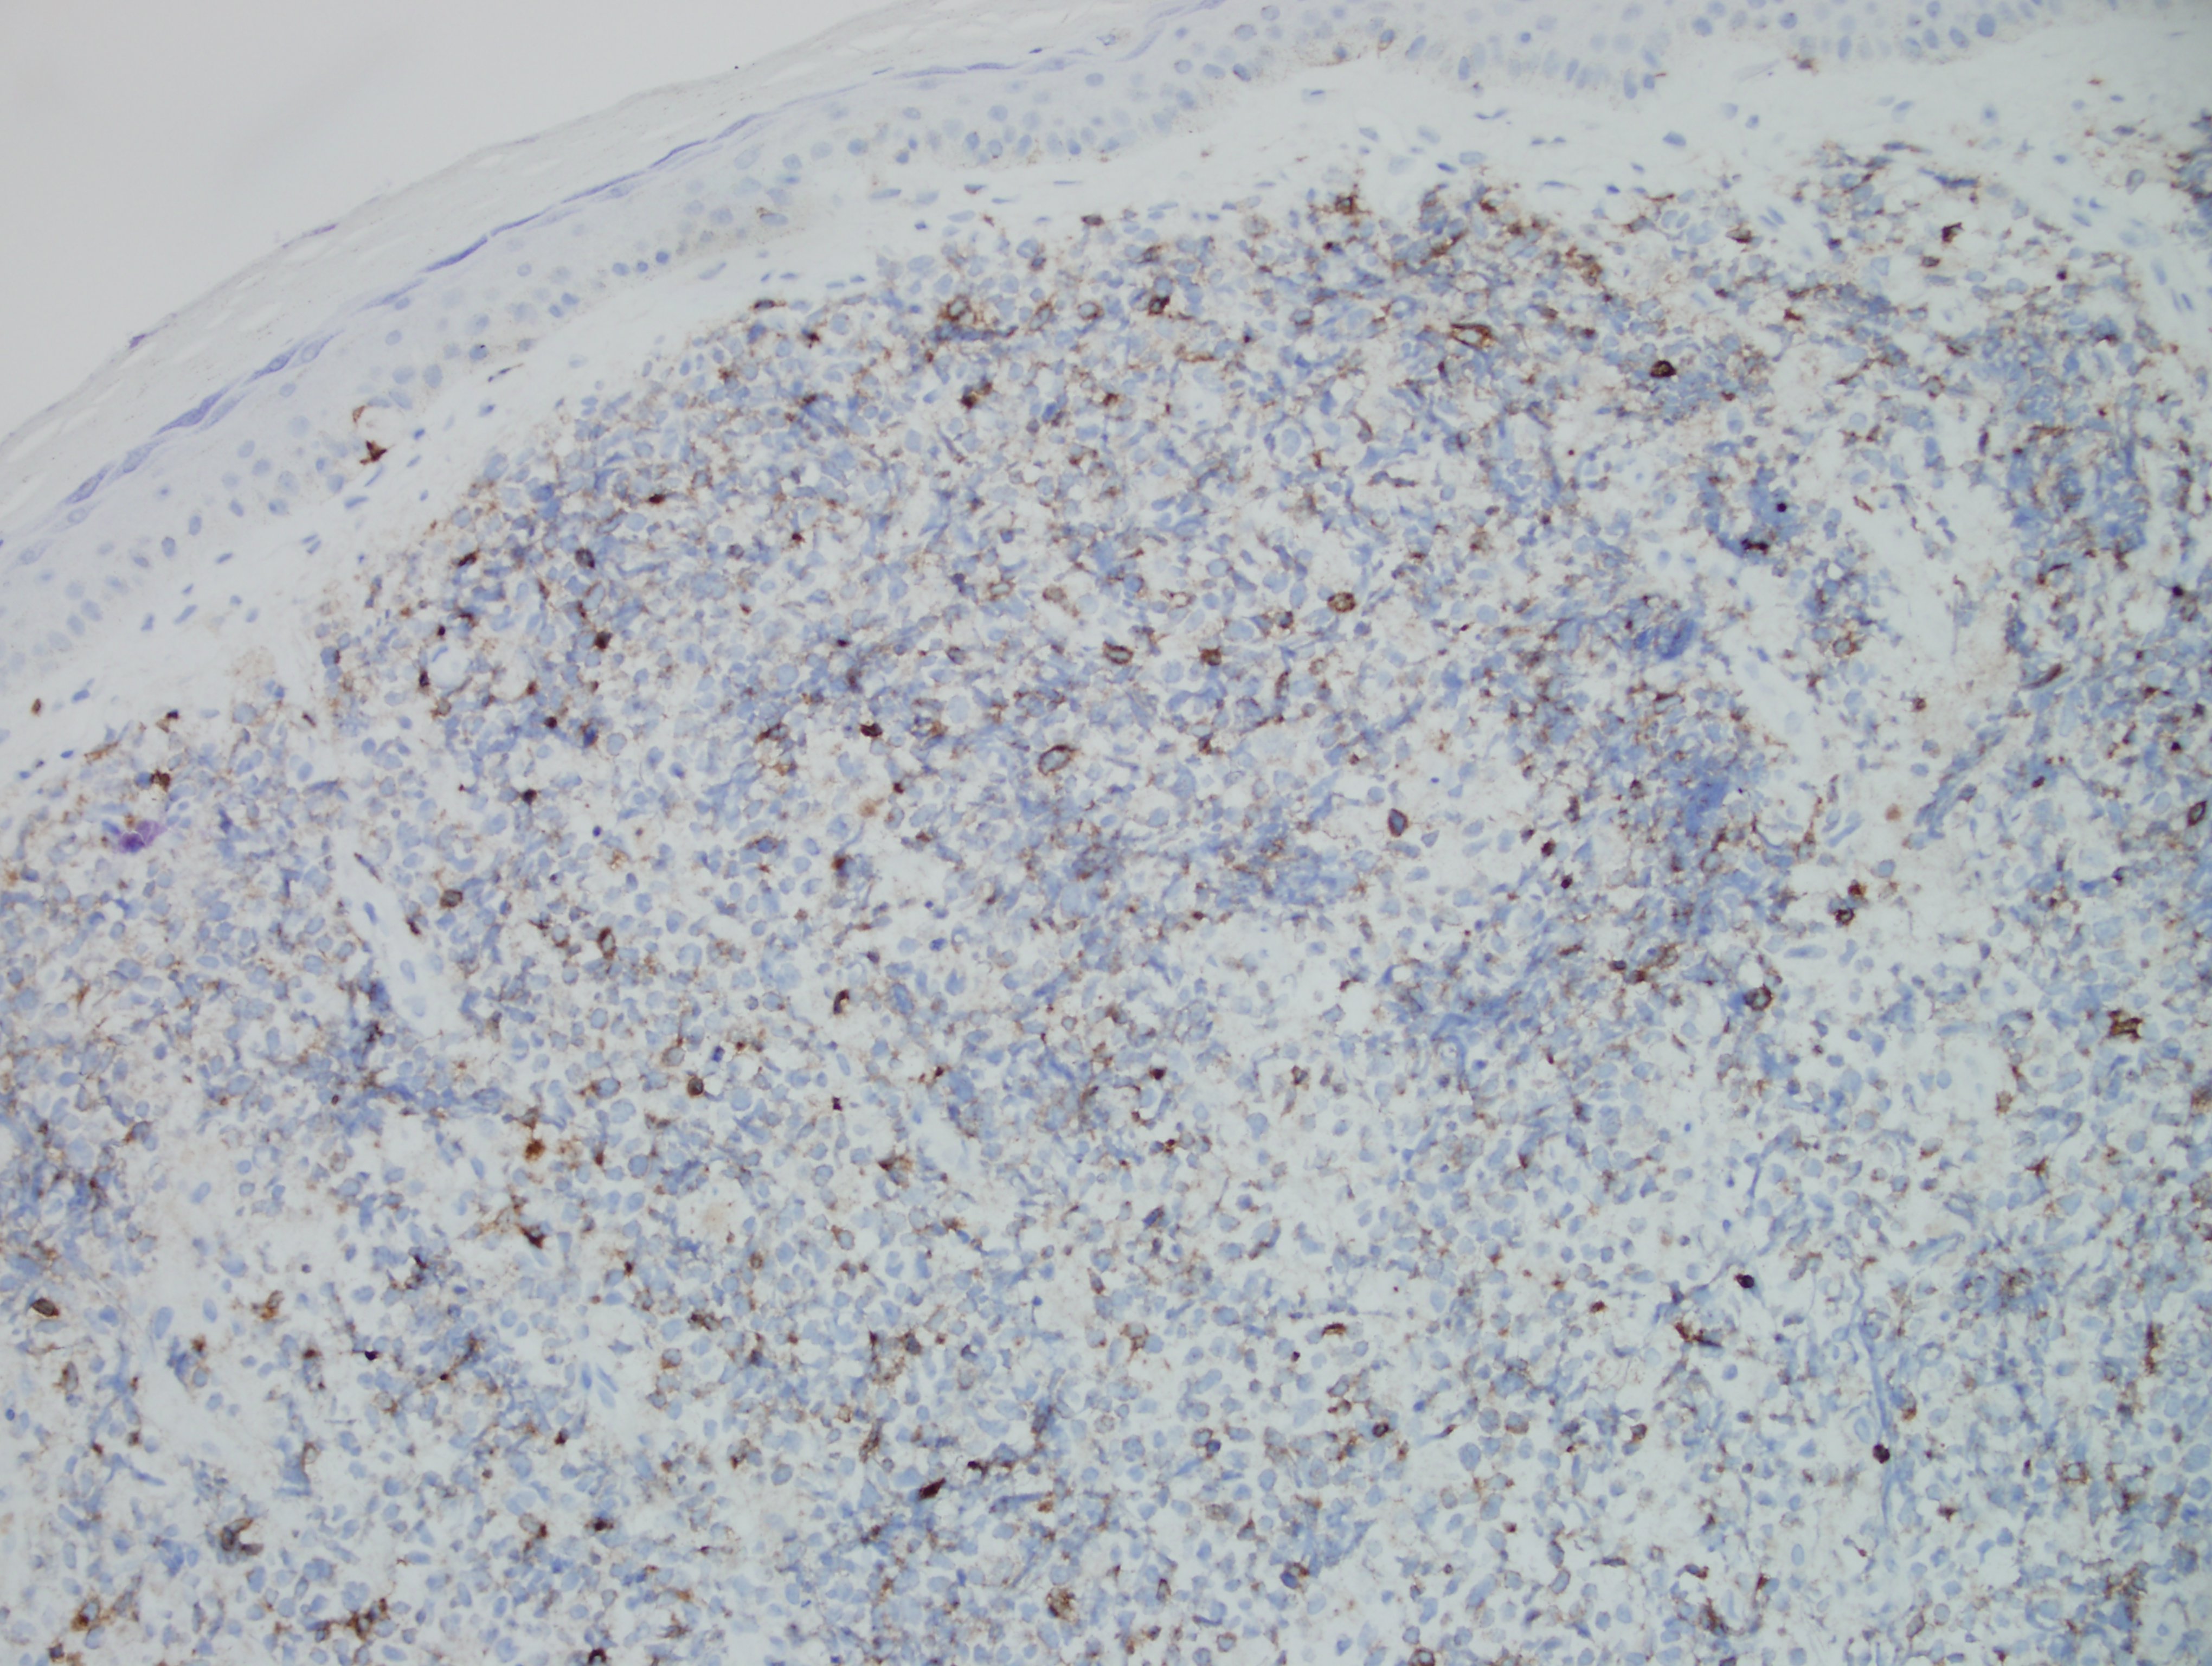

Morphologically, BPDCN is characterized by a diffuse infiltrate of blastoid, monomorphic and medium-sized cells with scant cytoplasm, irregular nuclei, fine chromatin, and nucleoli. Mitoses are typically present and necrosis is usually absent. With cutaneous manifestations, epidermotropism is not observed. Tumor cells typically express CD4, CD7+/-, CD56, CD123, CD303, TCL1, and CD43. Very rarely, CD56 can be negative. CD33, CD79a, BCL2, and BCL6 can also be expressed. T-cell and B-cell receptor genes are usually germline. Several recurrent chromosomal abnormalities have been noted, such as 5q21/5q34, 12p13, and 13q13-21.